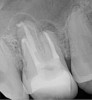

Figure 1. THROUGH Figure 3. Root filled with bioceramic sealer cut at different distances from the apex (left to right: 0.5, 1.5, and 3.0 mm). One gutta-percha point is used as a plugger to move the sealer using hydraulic pressure. Note the irregularities are very well filled.

Figure 1

Figure 2